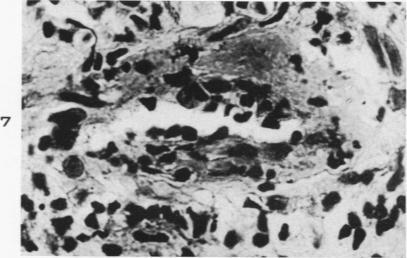

Asymptomatic focal arteritis of the appendix; 88 cases.

Am J Pathol. 1951 Mar-Apr;27(2):247-63.